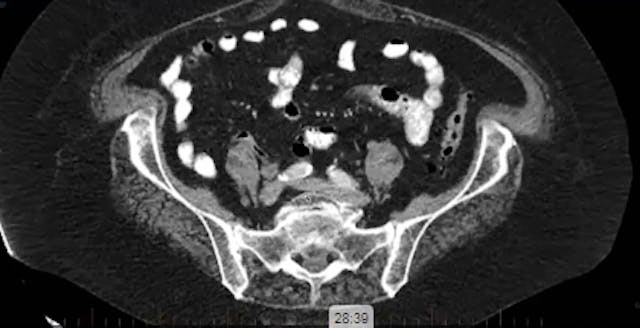

09/20/2023 - Dr. Christine Fisher - Radiation Oncology - GYN

chemotherapy, radiation therapy, sandwich regimen, brachytherapy, well differentiated endometrioid adenocarcinoma, neoadjuvant chemotherapy, small bowel, dilation, dosimetry, gross disease dose, MRI, cirrhosis, external beam radiation, Rotte Y applicator, CT scan, dual tandem, 3-D printing, endom...